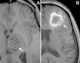

Subacute cephalohematoma

T1-hyperintense extracranial mass